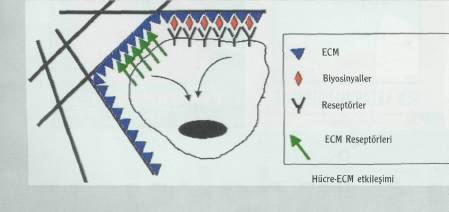

damarlarının organik bir iskeleti oluşturuluyor. Bu iskeleti oluşturduktan sonraki aşamaysa hücrelerin oluşturulması. Damar iskeleti çevresine yerleştirilen karaciğer hücreleri, belirli büyüme faktörleri yardımıyla çoğalarak organın kalın etli kısmını oluşturuyorlar. Bir sonraki aşamaysa damarın oluşturulması. Bunun için süngerimsi yapıda olan PLGA içine damar hücreleri enjekte ediliyor. İskelet, hücrelerin çoğalması için gerekli büyüme faktörlerini ve besin maddelerini içeriyor. Damar hücreleri iskelet boyunca ilerleyerek karaciğer hücrelerine yapışıyor. Burada çoğalan damar hücreleri, iskelet çevresinde birleşerek tam bir damar yapısı oluşturuyorlar. PLGA iskelet birkaç ay içinde kendiliğinden eriyerek geride karaciğer hücreleri ve içinde damarları olan yapay bir organ bırakıyor. Bu şekilde oluşturulan yapay karaciğer hayvanlarda denendi. Oldukça iyi kan akımının sağlandığı bu organlarda dışarı kan sızıntısı da gözlenmedi.

Tabii bu teknolojiyi ideal şekle getirmek çok kolay değil. Karaciğer içinde değişik görevleri olan milyonlarca hücre var. Yalnızca bir gram karaciğer dokusunda yaklaşık 100 milyon karaciğer hücresi bulunuyor. Hücrelerin gerekli noktalara yerleştirilmesi ve buradaki konumlarını korumalarının sağlanması oldukça güç. Yapay karaciğer oluşturulmasında karşılaşılan diğer bir güçlükse, organın mikroplardan arındırılması. Yapay organların içine hiçbir mikrobun girmemesi gerekiyor. Bu nedenle, çalışmalarda kullanılan tüm cihaz ve aletlerin steril, yani mikroptan arındırılmış olmaları çok önemli.